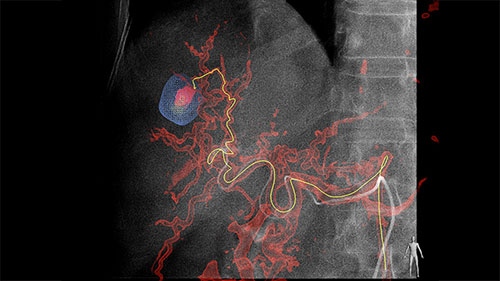

Live Image Guidance then supports selective or super-selective approaches to the embolization target.

Guidance EmboGuide 1 LM